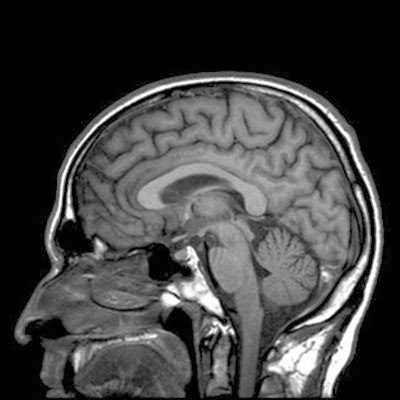

La dyslexie, un problème de cerveau déconnecté

Pour répondre à cette question, ils ont recruté 45 adultes dont 23 souffrant de dyslexie, et ont observé leurs cerveaux par imagerie par résonance magnétique (IRM) pendant qu’ils écoutaient différents sons. Leurs résultats n’ont montré aucune différence d’activité cérébrale. « Cela suggère que le cerveau des personnes dyslexiques entend les sons de la même façon que les autres », explique Sophie Scott, une des participantes à l’étude.

Dans une autre expérience, les scientifiques ont voulu explorer les connexions cérébrales mises en jeu lors de l’écoute de sons. Ils se sont particulièrement intéressés à 13 zones du cerveau, connues pour participer au langage et ont observé les structures qui les connectent entre elles. Ils se sont alors rendu compte que dans les cerveaux des participants dyslexiques, le gyrus temporal supérieur, la région contenant le cortex auditif, n’était pas correctement lié au gyrus frontal inférieur, une zone impliquée dans le développement du langage et de la parole. « On pourrait donc décrire la dyslexie comme un trouble qui déconnecte le cerveau », indiquent les chercheurs.

Les auteurs ont également montré que plus cette connexion était déficiente, plus les troubles dyslexiques étaient importants. Selon leurs données, l’évaluation du niveau de fonctionnalité de cette liaison cérébrale permettrait de prédire les risques de dyslexie avec une précision de 73 %.

« Cette étude montre que lorsque l’on étudie une maladie du système nerveux, on ne peut pas uniquement regarder les régions cérébrales indépendamment les unes des autres, raconte Sophie Scott. Il est important d’analyser le cerveau dans son ensemble et d’observer la manière dont les différentes zones du cerveau communiquent entre elles. » Cette étude ouvre la voie vers une piste de traitement contre la dyslexie. Dans le futur, les chercheurs souhaiteraient trouver des solutions pour améliorer les connexions qui fonctionnent mal et soigner ce trouble invalidant.